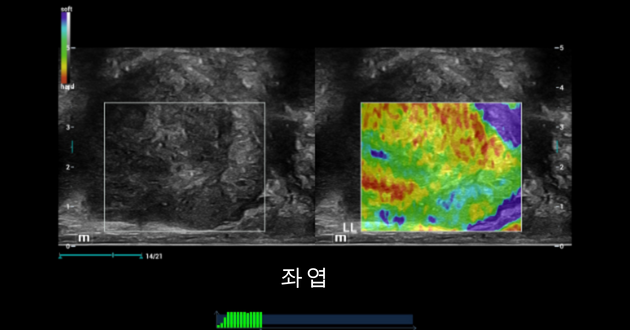

형상3. 좌엽 TRUS는 일부 정상 소견을 보여주었습니다: 의심스러운 결절 부위는 없음, 정상적인 도플러 사인이었으나 전립선 캡슐은 정상적으로 선명하고 매끄럽지 못함.

Prostate shearwave left lobe

형상5. 좌엽에 대한 소견은 전이부위(TZ)와 전립부위(PZ)사이의 경계가 명확하게 구분되는 전형적인 정상 소견. 전립 탄성 초음파는 정상적이었음.

형상7. 전단파 탄성 초음파(SWE)는 전립부위(PZ)의 정상적인 연탄성도를 포함한 전립선 좌엽의 일부 정상 소견을 발견. 전이부위는 고령 환자의 전립부위보다 단단하여 전립부위와 전위부위의 구분이 명확하였다.